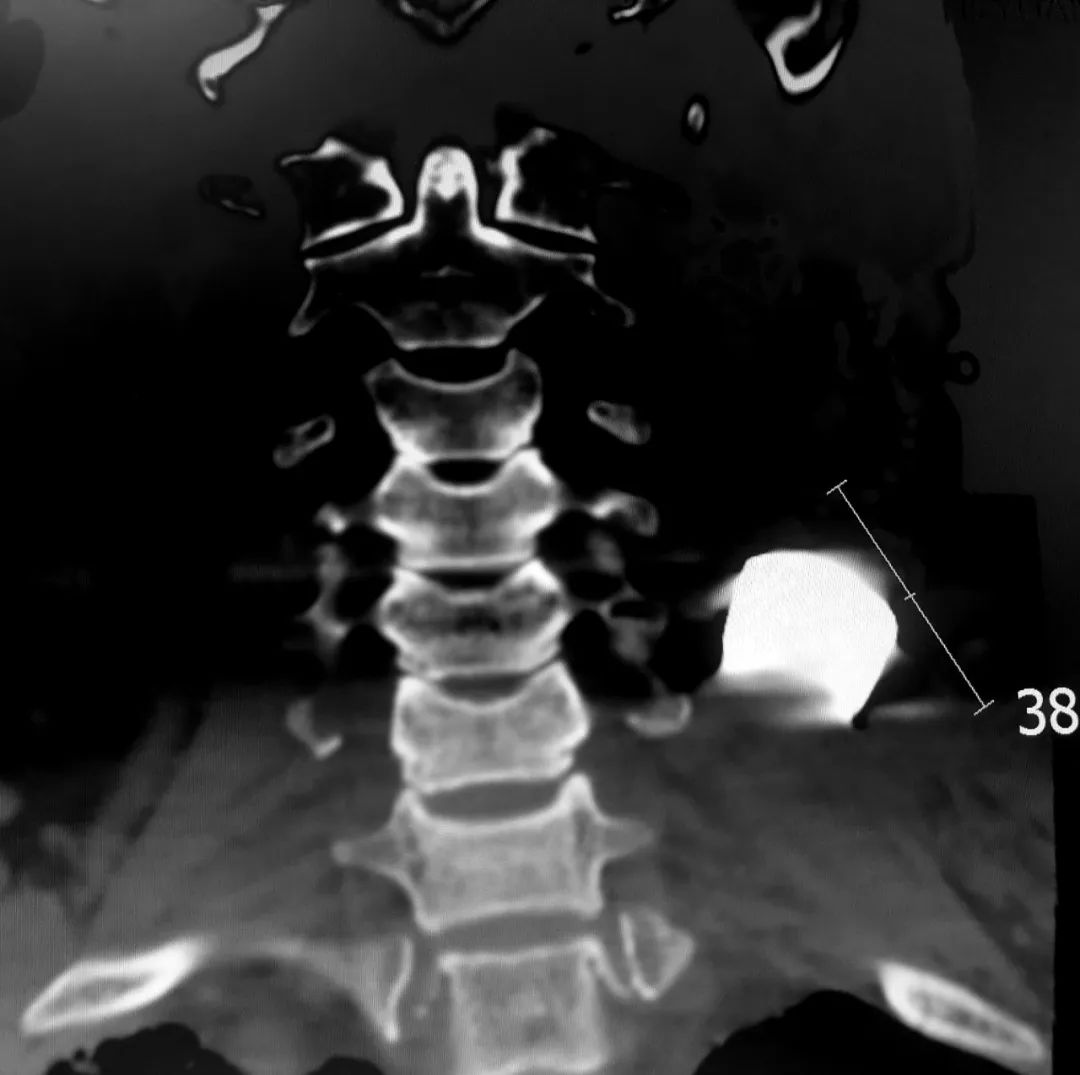

患者术前CT片

患者术前三维CT

患者为老年男性,被金属异物从胸壁射入造成一处大小约6cm×8cm的伤口,金属异物残留在颈部,导致患者锁骨开放性骨折、肋骨多发骨折,并出现肺挫伤,出血量大,送至我院时已出现失血性休克,病情危重。